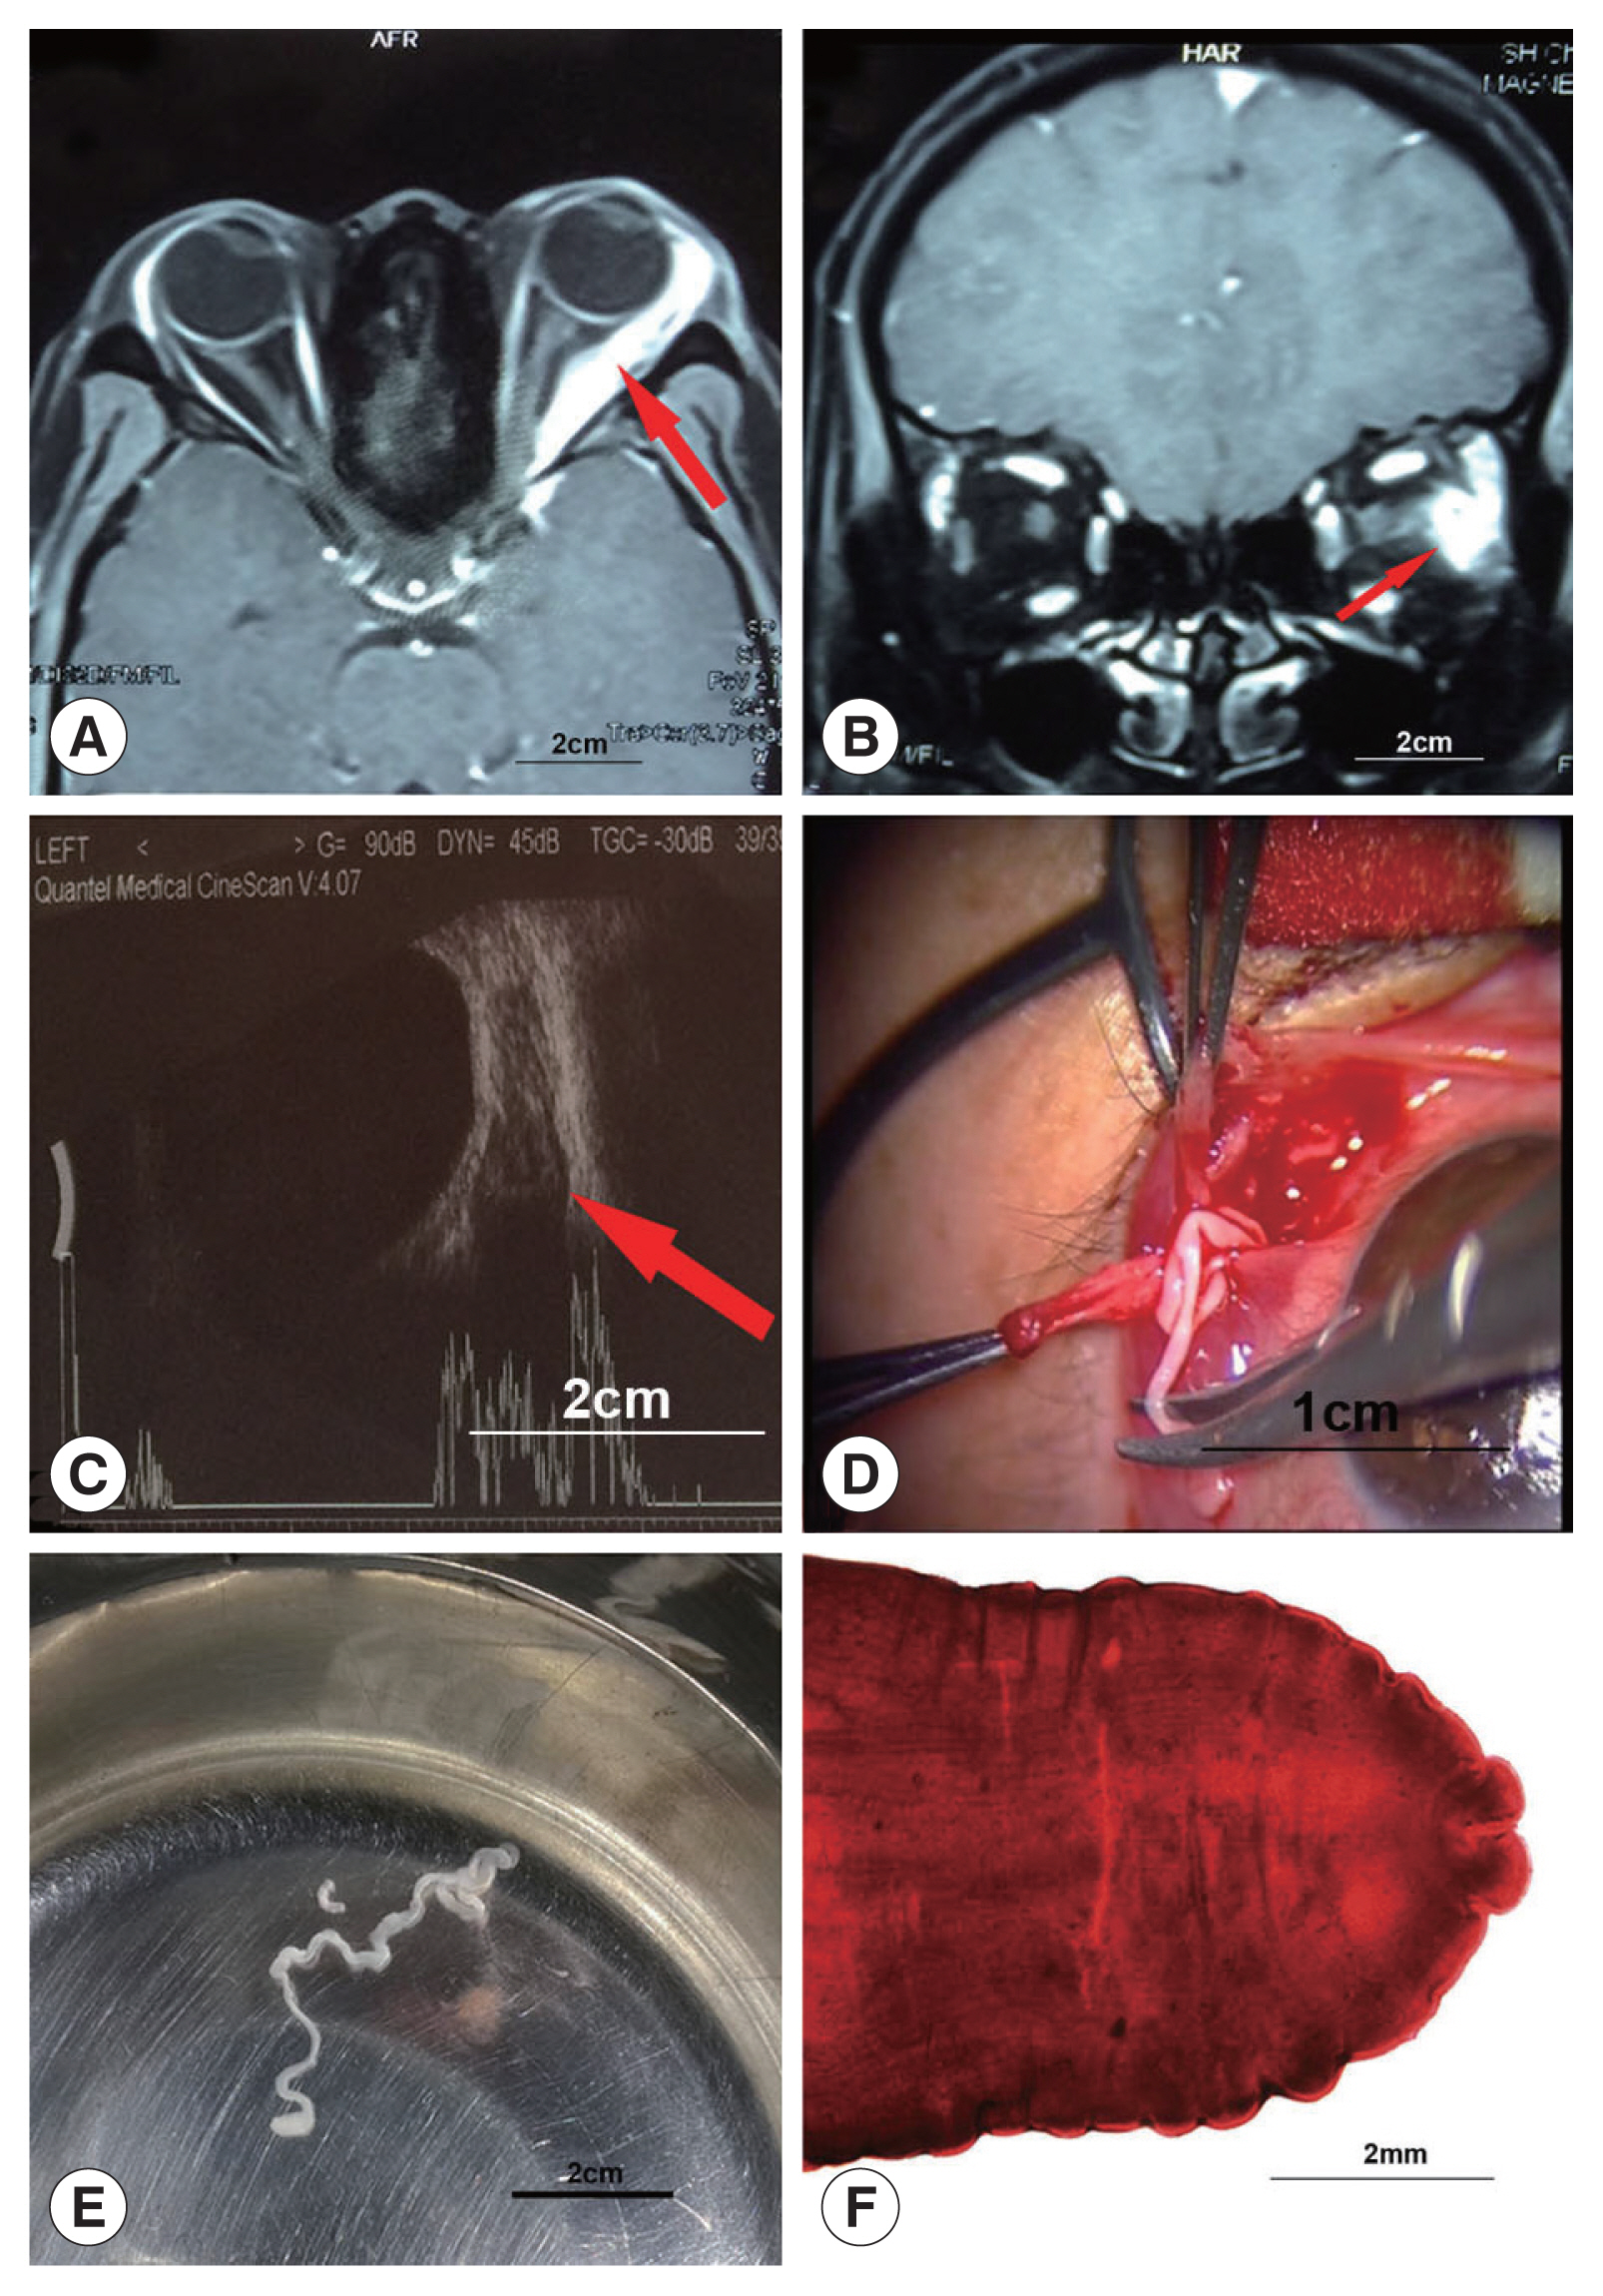

In December 2019, a 34-year-old woman visited our hospital with the complaints of conjunctival blood suffusion and recurrent pain in her left eye. She had no systemic or visual symptoms. She had a history of using pond water to wash her face and eating undercooked frog meat. The patient’s left eyeball was slightly protruding, but ocular motility was normal. The other ophthalmological examinations, including the fundus and visual acuity, were within the normal ranges for both eyes. The thyroid-related indexes, electrocardiogram, radiographic images of the lungs, renal function, and liver function indicated no abnormalities. A magnetic resonance imaging (MRI) scan from another hospital showed a foreign body in the muscle cone close to the lateral rectus in the left eye. On T1-weighted MRI, high signal, extending from the ocular attachment of the lateral rectus muscle to the depth of the orbit, very close to the optic nerve, was detected (Fig. 1A, B). On ultrasonography of the left eye, abnormal signals and an irregular hypoechoic mass with distinct borders were observed in the posterior part of the eyeball (Fig. 1C). The patient refused surgery to remove the lesion because of the possibility of damage to vision. As parasitic space-occupying lesions in the orbit are rare, we did not consider a parasitic infection in the initial diagnosis.

Two months later, the patient returned and explained that she experienced a creeping sensation in the left eye. Slit-lamp examination revealed a visible ribbon-like white foreign body under the conjunctiva in the left eye. Surgical exploration recovered a parasite (Fig. 1D). The extracted worm was approximately 8 cm in length, 2 mm in width, white in color, wrinkled, and ribbon shaped. The worm had a slightly enlarged head (Fig. 1E). The worm sample was morphologically identified as a plerocercoid larva (sparganum) of Spirometra tapeworm (Fig. 1F). Due to improper preservation of the parasites, molecular biological analysis could not be conducted, and the specific identity of the sparganum was not clear. The conjunctival blood suffusion and eye pain ceased 1 week after the operation. At 2-year follow-up, both eyes were examined using computed tomography (CT). No recurrence was found.